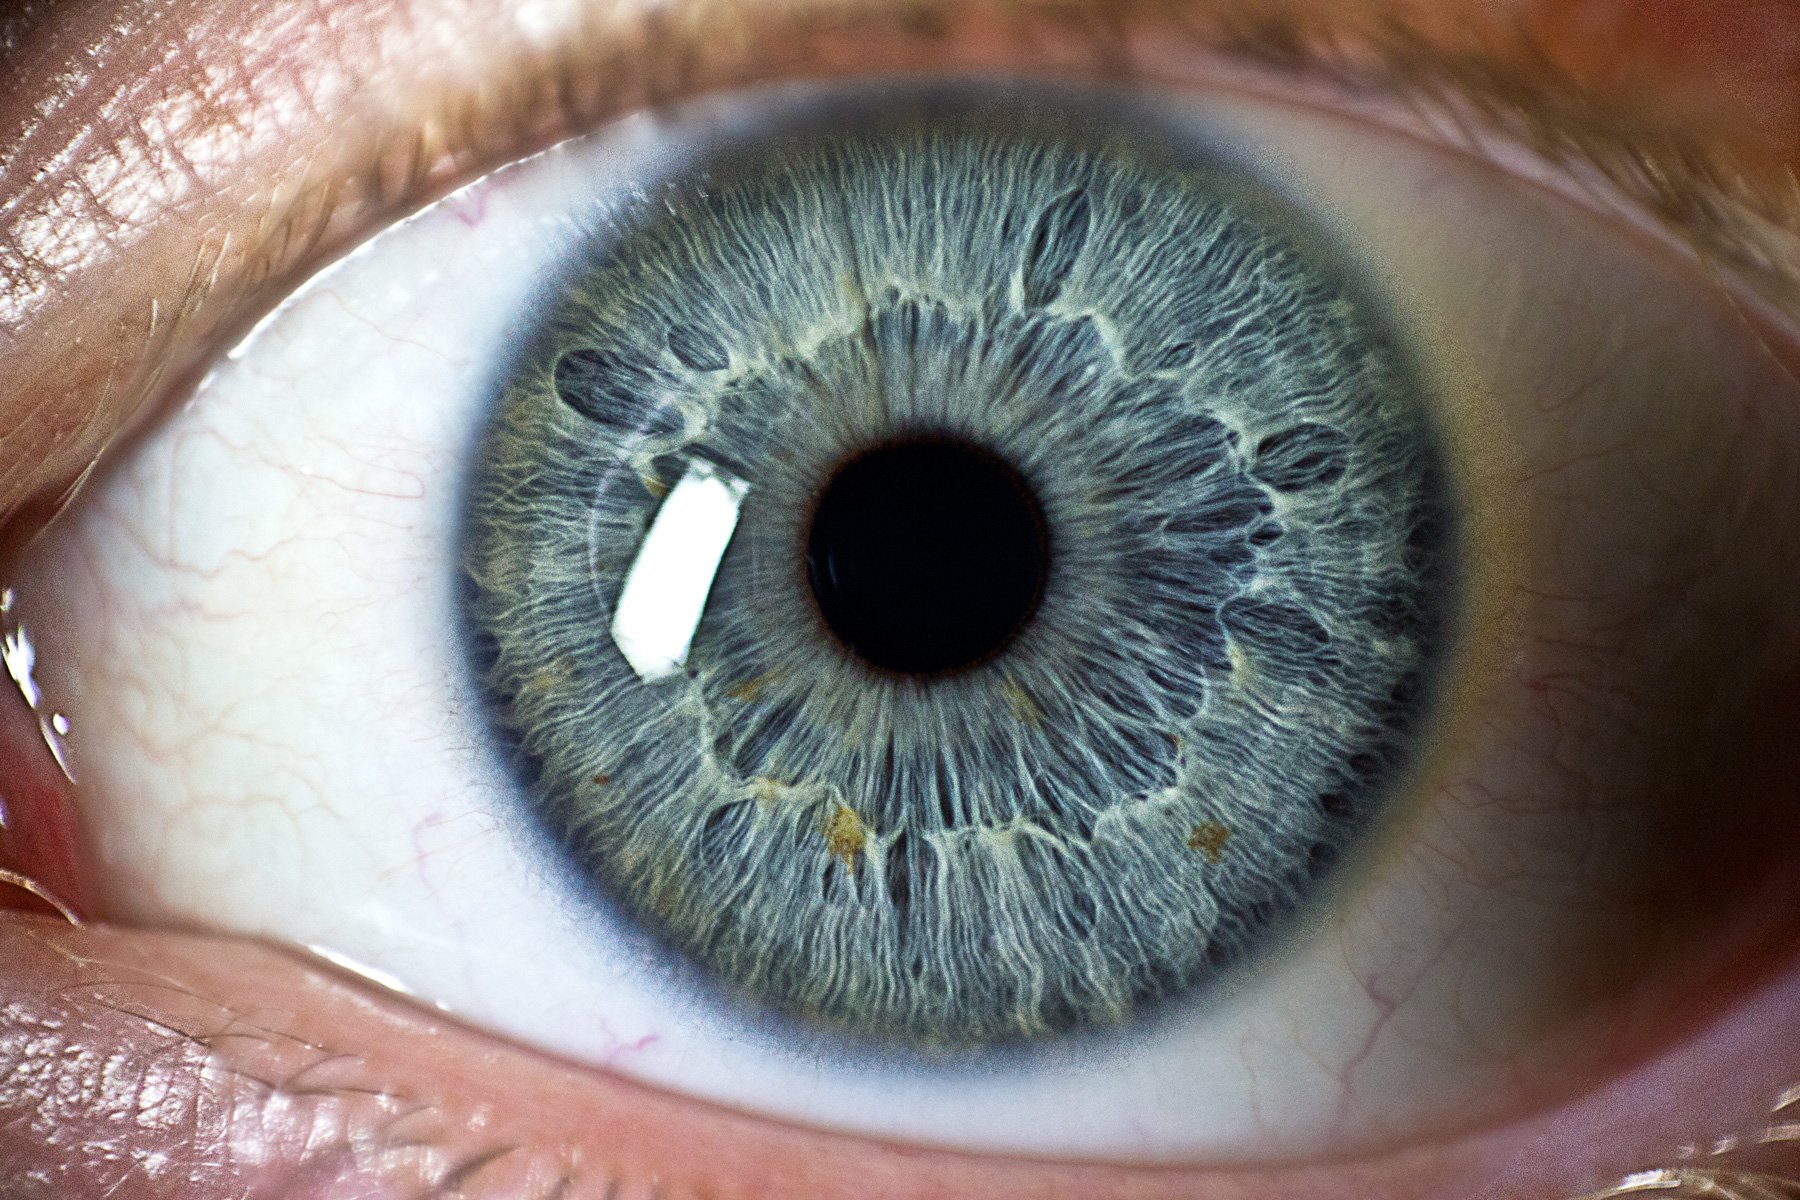

تكر مجموعة من العلماء بولاية كاليفورنيا الأميركية نوعية خاصة من قطرة العين يمكن أن تمنح الإنسان القدرة على الرؤية الليلة مؤقتا.

واعتمد العلماء في منظمة "Science for the Masses" في ابتكارهم على فكرة أن المركب الطبيعي "Chlorin e6"، واختصاره "Ce6"، الذي يمكن إنتاجه من الطحالب والنباتات، قد يعزز من قدرة الإنسان على الرؤية في الأماكن المعتمة.

وبحسب تقارير صحفية فإن المركب يمثل أساسا لبعض علاجات السرطان، ويستعمل كعلاج لمرض العشى الليلي.

وجرت تجربة 50 ميكرو لتر من "Ce6" على عين أحد الباحثين، وكان مفعوله فوريا، حيث تمكن من تمييز العديد من الأشكال في بيئة معتمة، وبمرور الوقت ازدادت المسافة لتصل إلى 50 مترا.

كما أجريت نفس التجربة على مجموعة اختبار لم تحصل على نفس المركب، ولم تتمكن من تمييز سوى ثلث ما ميزه الباحث، الذي بلغت نسبة نجاحه 100%.

ويستمر تأثير "Ce6" لبضعة ساعات، وتعود القدرة على الرؤية إلى طبيعتها بعد ذلك.

ونشرت المنظمة على موقعها الإلكتروني ورقة بحثية تكشف فيها عن تفاصيل التجربة، مؤكدة أنها تحتاج للمزيد من الأبحاث مستقبلا لمعرفة مدى التحفيز الذي يمنحه المركب للعين، وآثاره على المدى الطويل.